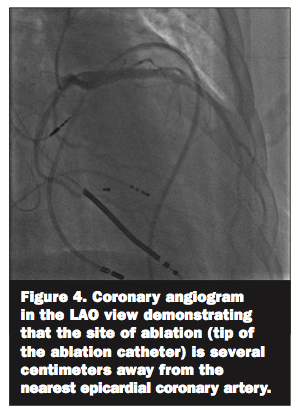

preceeding the onset of the QRS by approximately 100 ms (Figure 3). Entrainment mapping near that location demonstrated concealed entrainment with a post-pacing interval minus tachycardia cycle length of 15 ms (Figure 1). Coronary angiography showed that the earliest site was several centimeters away from the epicardial coronary arteries (Figure 4). Ablation at this site resulted in immediate VT termination. Radiofrequency energy was delivered at an initial power of 30 W and was gradually titrated

Radiofrequency catheter ablation has become an important tool for the successful management of patients with refractory ventricular arrhythmias. Endocardial ablation success rates are variable, ranging from 50-80%,2,3 and nearly one-third of all VT circuits are inaccessible from the endocardium due to epicardial or intramural locations. Thus, epicardial ablation has emerged as an essential modality for VT ablation, especially in patients with non-ischemic cardiomyopathy who are more likely to have epicardial substrates. As mentioned earlier, the index of suspicion that this VT originated from the epicardium was high given the history of dilated non-ischemic cardiomyopathy. Furthermore, his VT demonstrated delayed intrinsicoid deflection consistent with an epicardial origin.7 Accordingly, pericardial access was obtained prior to heparin administration and endocardial mapping. As demonstrated in this case and in contradistinction to patients with ischemic heart disease, the area of epicardial scarring is often much larger than endocardial scar in patients with non-ischemic cardiomyopathy, and it is usually not confined to a specific coronary vascular territory.4-6 Since its introduction by Sosa and colleagues,1 transcutaneous epicardial access has been gaining wider acceptance. Epicardial substrates have been increasingly recognized in all types of VT including infarct/scar related VT, idiopathic VT, arrhythmogenic right ventricular dysplasia, and non-ischemic cardiomyopathy.4-8 A recent study9 reported that approximately 13% of patients with VT require epicardial ablation. The highest prevalence of epicardial VT circuits is in patients with arrhythmogenic right ventricular cardiomyopathy (41%) and nonischemic cardiomyopathy (35%), followed by ischemic heart disease (16%). Thus, it is becoming increasingly apparent that epicardial involvement may be higher than previously appreciated, especially in certain substrates and in the setting of previously failed endocardial ablation. The percutaneous subxiphoid approach to access the pericardium remains challenging. However, in experienced hands, epicardial VT ablation can be performed effectively and safely. Failure to obtain epicardial access occurs in approximately 10% of cases and is most often related to pericardial adhesions in the setting of a history of cardiac surgery. Diagnostic mapping is performed in a similar fashion to endocardial mapping. However, pace- and entrainment mapping may be limited by poor capture thresholds due to the presence of pericardial fat. Similarly, it may be difficult to differentiate low voltage due to true scar from that due to epicardial fat, and this may limit substrate mapping. In general, electrograms in areas of scar demonstrate low voltage (9 reported that 71% of patients were free from VT recurrence after a mean follow-up period of 23 months. This is similar to other published case series reporting success rates from 63% to 78%.4,6,8 Major complications include hemopericardium as well as injury to subdiaphragmatic vessels and damage to the ventricles, epicardial coronary arteries or left phrenic nerve. In the retrospective multicenter safety study by Sacher et al, acute major complications (mainly pericardial bleeding that required intervention) occurred in 5%, and delayed complications occurred in 2%.9 Coronary angiography is usually performed prior to radiofrequency lesion application in order to ascertain the distance from coronary vessels. Although data are lacking, a distance of ≥ 1 cm from the ablation catheter to the coronary artery is generally considered to be relatively safe. In addition, high-output pacing is performed prior to ablation on the lateral left ventricular wall in order to avoid injury to the left phrenic nerve. Pericarditic discomfort is very common following the procedure, leading some investigators to inject glucocorticoids in the pericardial space prior to catheter removal in hopes of preventing pericarditis and reducing subsequent fibrosis. The presence of pericardial adhesions, as is seen following cardiac surgery, can significantly hinder access and catheter movement. These patients often need a direct surgical approach to the pericardial space. In conclusion, catheter epicardial VT ablation is emerging as a practical alternative to conventional endocardial catheter ablation of VT in certain selected patients. With more experience, substrate recognition, and appropriate patient selection, this procedure is likely to gain wider acceptance as a safe and effective treatment option for patients with incessant VT that might not otherwise respond to an endocardial approach alone.References